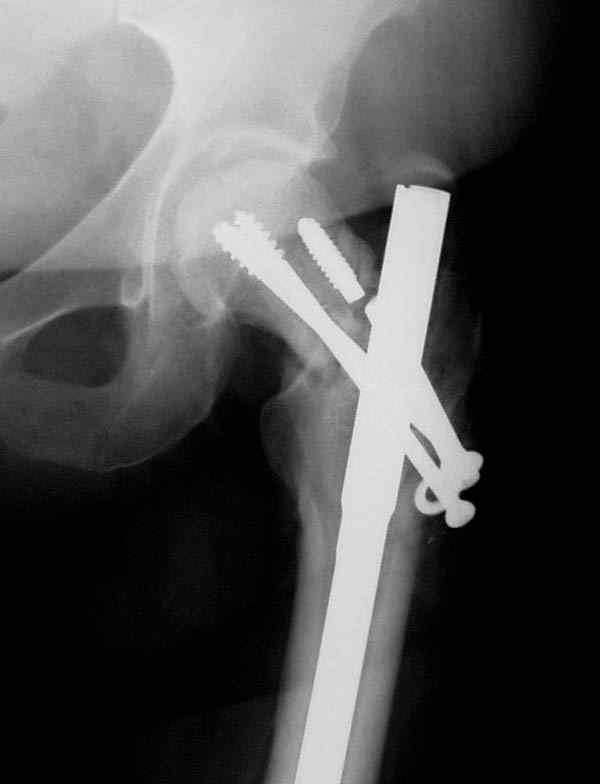

Несмотря на пессимистические прогнозы, у молодых

коррегирующая вальгусная остеотомия является более

приемлемым.

Представленные случаи доказательства тому, что еще

имеется резервы на восстановление даже у 5-6 месячных ложных суставов шейки.